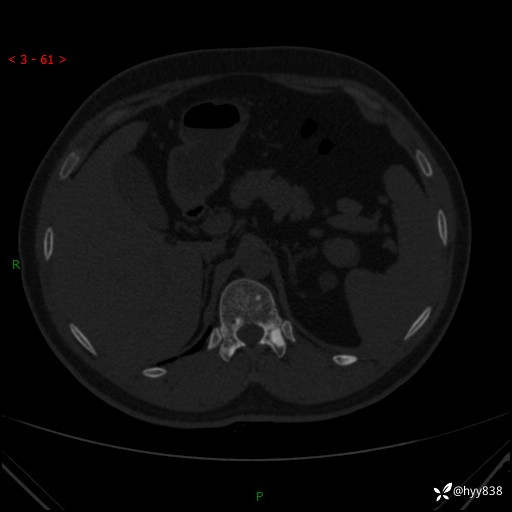

患者性别:男

患者年龄:28岁

简要病史:右肾肿瘤术后,常规复查

辅助检查:CT

临床诊断:右肾肿瘤术后

腹部CT+颅脑CT平扫